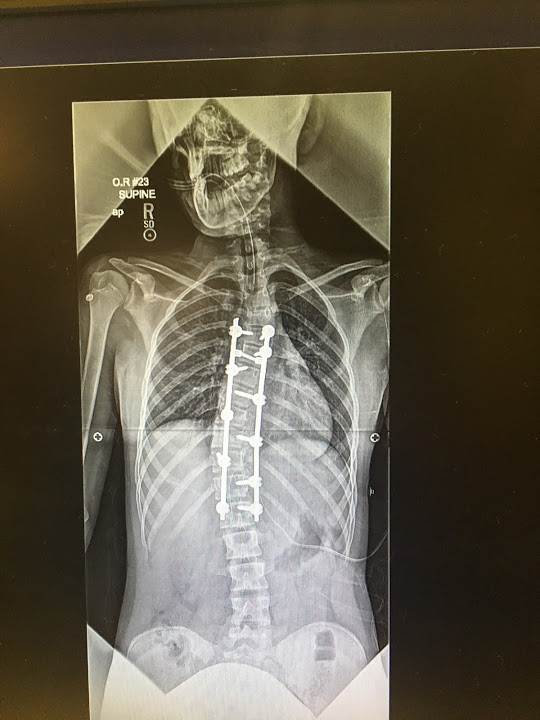

I had an amazing experience at HSS. I was 14 when I had to get a spinal fusion due to an excessive scoliosis curve of over 60 degrees. Dr. Lebl and the staff did an amazing job making sure I was comfortable during my surgery. If I went back in time I would not change a thing I loved my experience at HSS. They had me feeling like myself again within a few weeks, and I was back on the lacrosse field just after 3 months!